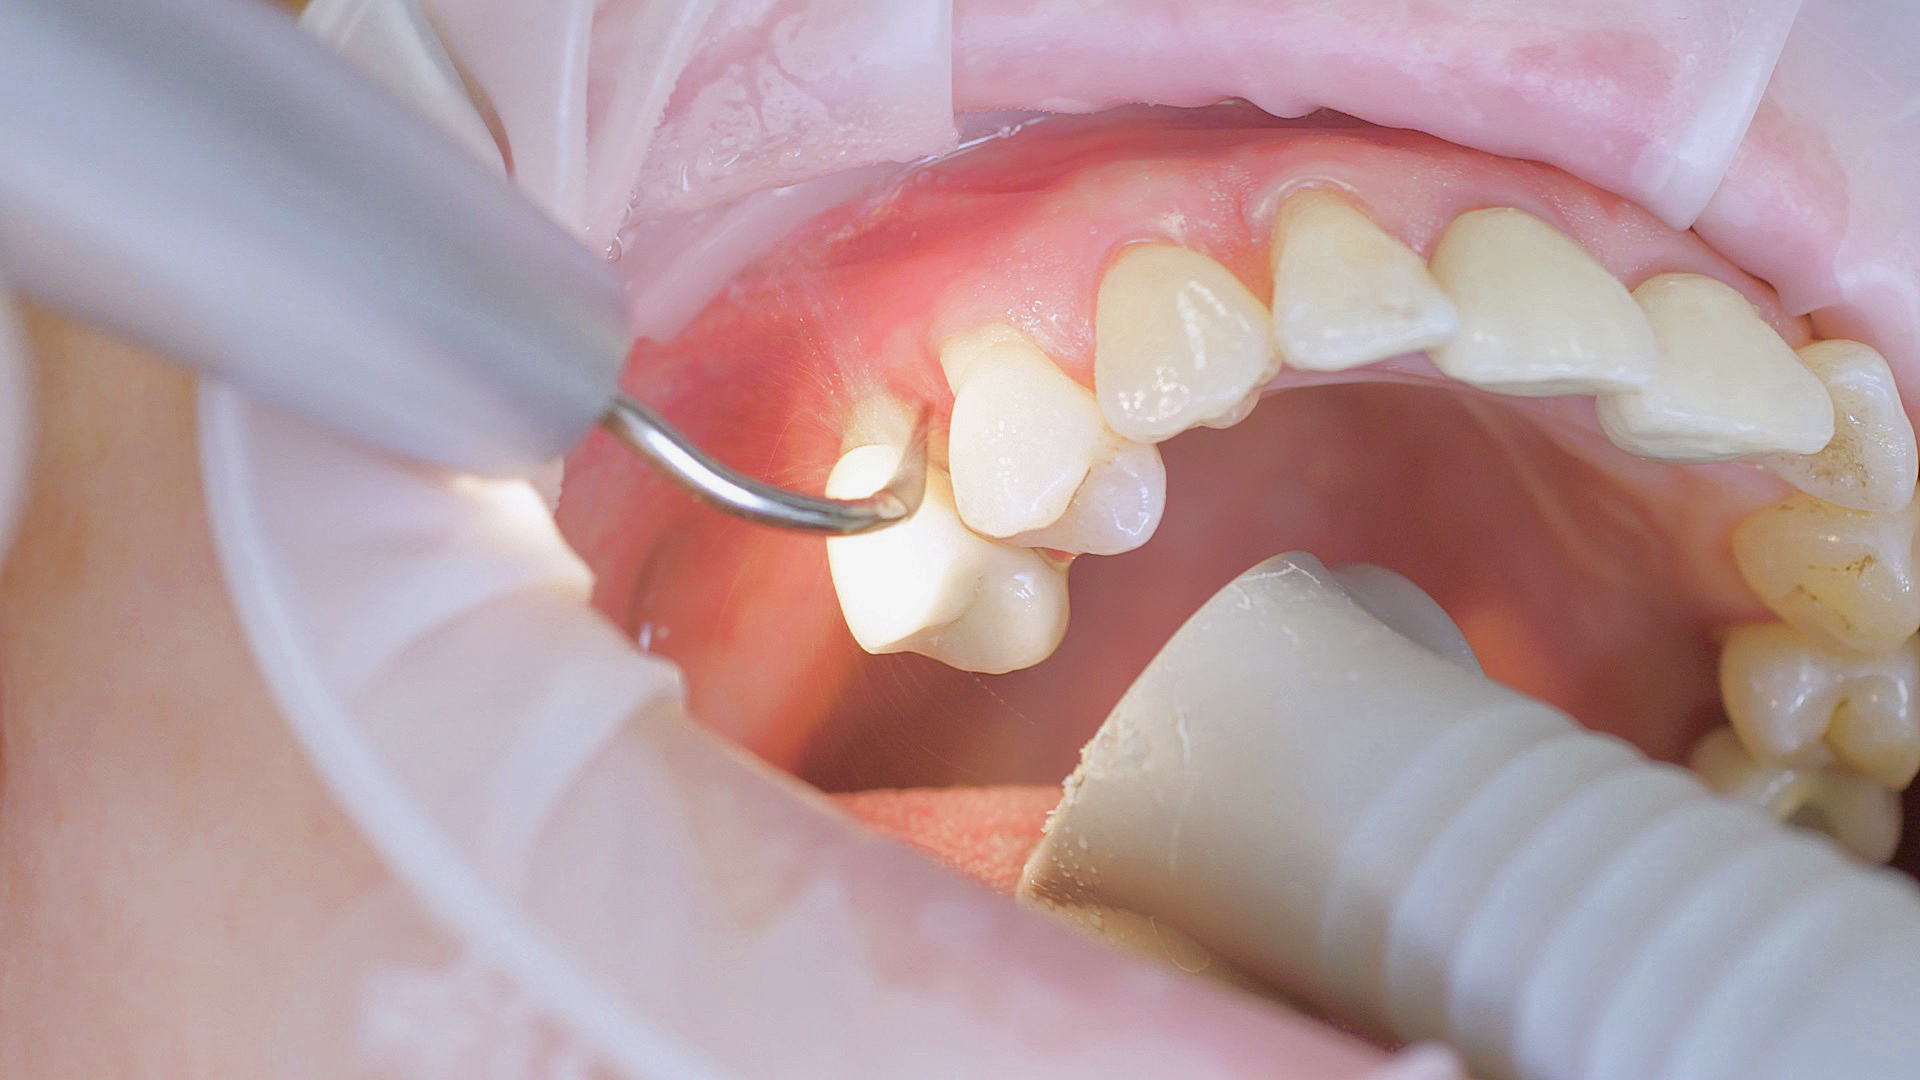

Where necessary, initial periodontal treatment is carried out. First, professional tooth cleaning establishes healthy gingival conditions. In this procedure, calculus (Fig. 1) and biofilm (Fig. 2) are removed as far as the gingival sulcus. In combination with careful instruction on oral hygiene, this gives the patient the basis for long-term freedom from inflammation.15

Removal of subgingival coatings (debridement) is carried out using sonic or ultrasonic devices and special periodontal tips as initial periodontal treatment (Fig. 3). Manual instruments can also be used. Further surgical and/or regenerative measures may be necessary, depending on the situation.

Sonar technology, W&H Proxeo with 1AP tip

Fig. 3: If marginal periodontitis is diagnosed, the initial debridement can be carried out very efficiently with an air scaler (sonar technology, W&H Proxeo with 1AP tip)